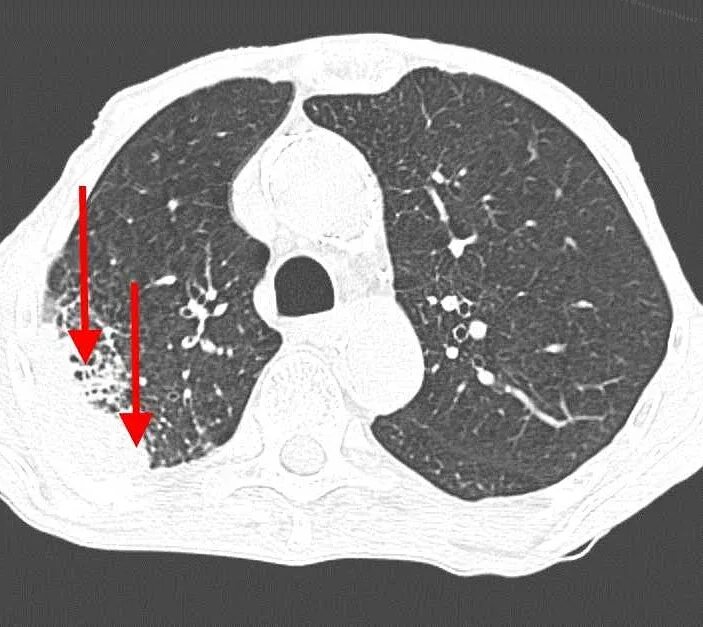

Как на кт выглядит рак